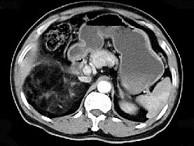

问题 男,59岁,右侧腰背酸痛,CT检查如图所示,应诊断为 ( )

选项 A、右腹膜后脂肪瘤 B、右肾血管平滑肌脂肪瘤 C、右肾上腺转移瘤 D、右肾上腺髓样脂肪瘤 E、右肾上腺腺瘤

答案 D